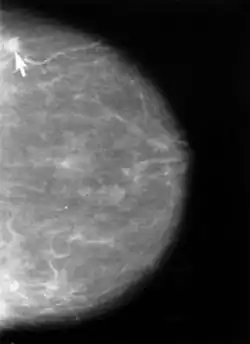

Bildgebende Verfahren

Die Röntgen-Mammographie ist einer S3-Leitlinie von 2010 zufolge zurzeit die einzige für die Erkennung von Brustkrebsvorstufen oder frühen Tumorstadien allgemein als wirksam anerkannte Methode.[91] Die Mamma-Kernspintomographie ist möglicherweise überlegen, jedoch für ein Massenscreening zu teuer.[92] In Deutschland wurde deshalb ein qualitätsgesichertes Mammographie-Screening-Programm auf der Grundlage der „Europäischen Leitlinien für die Qualitätssicherung des Mammographie-Screenings“ für Frauen von 50 bis 69 Jahren aufgebaut. Dazu wurde Deutschland in 94 Regionen aufgeteilt, für die jeweils eine Screening-Einheit verantwortlich ist.[93] 2024 wurde das Mammographie-Screening in Deutschland auf Frauen von 50 bis 74 Jahren ausgeweitet. In den USA gab es 2002 die Empfehlung, das Mammographiescreening bereits mit 40 Jahren zu beginnen.[88]

Die Mammographie ist bei Frauen mit dichtem Drüsengewebe in ihrer Aussagekraft begrenzt. Bei extrem dichtem Gewebe werden etwa 50 % der Brusttumoren mit der Mammographie nicht entdeckt. Dies betrifft in erster Linie jüngere Frauen, denen die Sonographie, im Einzelfall auch Kernspin-Mammographie, empfohlen wird. Nach systematischer Literaturrecherche bewertet der IGeL-Monitor (Initiator und Auftraggeber: MDS (Medizinischer Dienst des Spitzenverbandes Bund der Krankenkassen)) die Sonographie (Ultraschall) mit „unklar“, die Magnetresonanztomographie (MRT, Kernspin) mit „tendenziell negativ“. Die Wissenschaftler des IGeL-Monitors fanden in beiden Fällen keine Studien, die die Frage untersucht haben, ob die Untersuchungen Frauen tatsächlich davor bewahren können, an Brustkrebs zu sterben. Das gilt für die Untersuchungen zusätzlich zum Mammographie-Screening ebenso wie als Alternative zum Mammographie-Screening. Bei der MRT sind Schäden durch das Kontrastmittel möglich, das dabei gespritzt wird. Diese Bewertungen gelten für Frauen ab 40 Jahren, die kein erhöhtes Brustkrebs-Risiko haben.[96]

Bildgebende Diagnostik

Werden bei der Tast- oder Ultraschalluntersuchung Auffälligkeiten gefunden, folgt als nächste Untersuchung üblicherweise die Mammographie: Die Röntgenaufnahmen werden aus zwei Blickrichtungen (von der Seite und von oben) gemacht, bestimmte Veränderungen erfordern manchmal zusätzliche Aufnahmen. Die Galaktographie wird nur durchgeführt, wenn die Brustwarzen Sekret absondern. Als Ergänzung steht bei einer solchen Sekretion an einigen Zentren die Duktoskopie, eine Spiegelung der Milchgänge, zur Verfügung.

Umgekehrt werden mit der Mammographie entdeckte Veränderungen immer sonographisch weiter untersucht. Dabei werden gutartige Zysten erkannt. Die Kassenärztliche Bundesvereinigung schrieb 2003 hierfür Schallköpfe mit mindestens 5 MHz Frequenz vor.[101] Mittlerweile ist dieser Wert auf 7,5 MHz erhöht worden.[102]